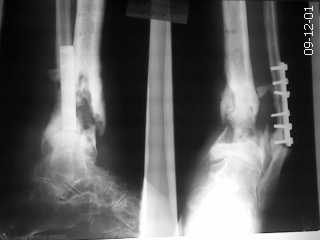

хронический остеомиелит н/3 голени |

Поступил пациент с хроническим остеомиелитом. варусной установкой дистального отломка.

Пациент 35 лет. Оперирован по поводу перелома в ЦРБ. В дальнейшем нагноение-удаление пластины большеберцовой кости. В настоящее время имеется варусная установка голени, укорочение конечности. Имеется рана с гнойным отделяемым. Ходит с помощью костылей. Рассчитывать на серьёзные материалы для лечения смысла нет, т.к. больной неплатежеспособен.

Фото прилагаю. Коллеги, у кого какие есть соображения по лечению? Буду очень признателен.